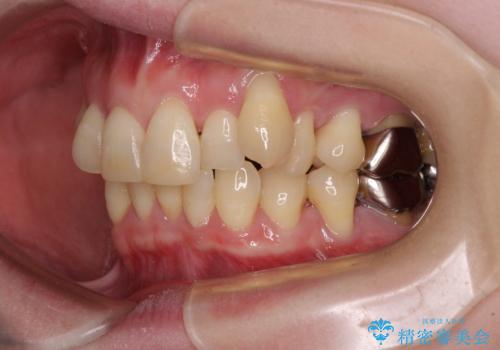

八重歯と先天欠損の歯列 ワイヤー矯正ですっきりと

- 八重歯と正中のズレを気にして来院された患者様です。

上顎左側が八重歯になっており、上顎正中が左側にずれていました。

上顎左側の第一小臼歯を抜歯し、補助装置を用いて正中位置を改善しながら八重歯を解消していくこととしました。

下顎前歯が1本欠損していたため、上下正中の位置が合わせるという目標はなく、鼻筋に上顎正中を合わせていくように移動を行いました。